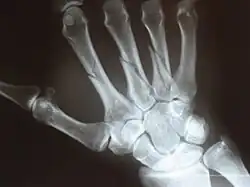

![]() Rentgen mnohočetných zlomenin záprstních kůstek pravé ruky | |

Záprstí (latinsky metacarpus) je skupina pěti záprstních kostí (ossa metacarpi, sg. os metacarpi), které tvoří kostru dlaně. Tvarově odpovídají dlouhým kostem, ale řadí se mezi krátké kosti (okolo 10 cm). Rozlišujeme na nich tři části:

- základna (basis) – proximální rozšířený konec záprstní kosti, nasedá na carpus;

- tělo (corpus) – tělo (odpovídá diafýze); má tři plochy: jednu zadní a dvě boční, které jsou směrem k dlani oddělené nevýraznou hranou;

- hlavice (caput) – distální rozšíření záprstní kosti, na ni nasedají ossa digitorum.

Všechny kosti jsou z dorsální strany dobře hmatné. Jsou očíslovány římskými číslicemi od I. do V. směrem od palce (v radioulnárním směru). Prostory mezi záprstními kůstkami se označují spatia interossea metacarpea.